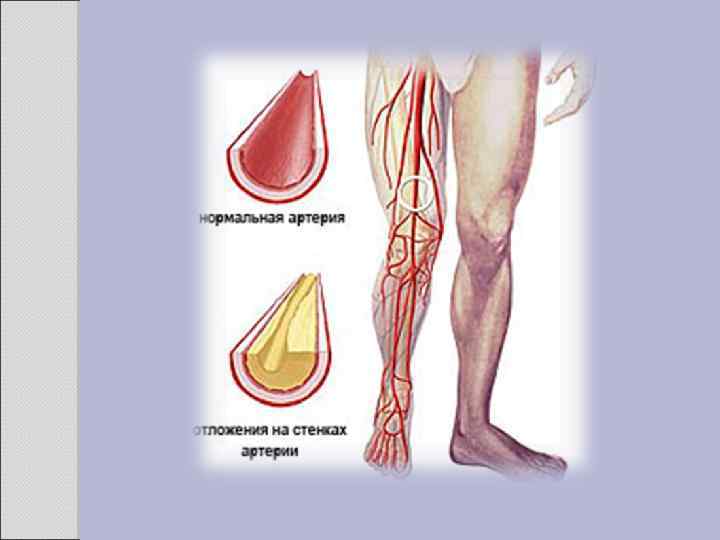

Клиника Клинические проявления часто не соответствуют морфологии. При патологоанатомическом вскрытии обширное и выраженное атеросклеротическое поражение сосудов может оказаться находкой. И наоборот, клиника ишемии органа может появляться при умеренной облитерации просвета сосуда. Характерно преимущественное поражение определенных артериальных бассейнов. От этого зависит и клиническая картина заболевания. Поражение коронарных артерий постепенно приводит к коронарной недостаточности, проявляющейся ишемической болезнью сердца. Заинтересованность церебральных артерий вызывает либо преходящую ишемию мозга либо инсульты. Поражение артерий конечностей — причина перемежающейся хромоты и сухой гангрены. Атеросклероз брыжеечных артерий ведет к ишемии и инфаркту кишечника (мезентериальный тромбоз). Также возможно поражение почечных артерий с формированием почки Голдблатта. Даже в пределах отдельных артериальных бассейнов характерны очаговые поражения — с вовлечением типичных участков и сохранностью соседних. Так, в сосудах сердца окклюзия наиболее часто возникает в проксимальном отделе передней межжелудочковой ветви левой коронарной артерии. Другая типичная локализация — проксимальный отдел почечной артерии и бифуркация сонной артерии. Некоторые артерии, например внутренняя грудная, поражаются редко, несмотря на близость к коронарным артериям и по расположению, и по строению. Атеросклеретические бляшки часто возникают в бифуркации артерий — там, где кровоток неравномерен; иными словами, в расположении бляшек играет роль локальная гемодинамика (см. патогенез).

Атеросклеротическое поражение аорты Гангрена правой нижней конечности.

Симптомы поражения нижних конечностей: • Перемежающаяся хромота, проявляющаяся болями в икроножных мышцах, которые появляются при ходьбе и исчезают после кратковременного отдыха. • При поражении крупных сосудов (брюшной аорты и подвздошных артерий) боли локализуются в голенях, ягодичных мышцах, поясничной области и мышцах бедер. • Одним из проявлений закупорки аорты является импотенция, обусловленная нарушением кровообращения в системе внутренних подвздошных артерий • Зябкость, повышенная чувствительность нижних конечностей к холоду, иногда чувство онемения в стопах. • Изменяется окраска кожных покровов ног. Вначале бледные, затем багровосинюшная (трофические нарушения). • С прогрессированием заболевания присоединяются зоны омертвения мягких тканей нижних сегментов пораженной ноги, сопровождающиеся отеком и багровой окраской стоп. • Выпадение волос, нарушение роста ногтей.

Клиника Диабетическая микроангиопатия нижних конечностей встречается в различных возрастных группах. Клиническая картина сходна с таковой при облитерирующем эндартериите. В то же время в течении ангиопатий имеются некоторые специфические особенности: • Раннее присоединение симптомов полиневрита различной степени выраженности (от чувства жжения и онемения отдельных участков или всей стопы до выраженного болевого синдрома). • Появление трофических язв и даже гангрены пальцев стоп при сохраненной пульсации периферических артерий. • Ангиопатия нижних конечностей, как правило, сочетается с ретино и нефропатиями. Клиническая картина диабетических макроангиопатий складывается из сочетания симптомов микроангиопатий и атеросклероза магистральных артерий. Среди последних чаще поражаются подколенная артерия и ее ветви. В отличие от облитерирующего атеросклероза диабетическая макроангиопатия нижних конечностей характеризуется более тяжелым и прогрессирующим течением, нередко заканчивающимся развитием гангрены. В связи с высокой подверженностью больных сахарным диабетом инфекции гангрена часто бывает влажной. Наличие симптомов ишемии нижних конечностей у больных, страдающих сахарным диабетом, дает возможность заподозрить диабетическую ангиопатию.